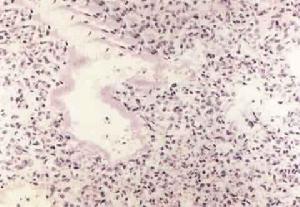

成人呼吸窘迫綜合徵ARDS時,病肺重量增加,呈暗紅色或暗紫色的肝樣變,肺泡含氣量少或不含氣。鏡下見肺微血管淤血、血流停滯,微血栓形成及小灶性出血。肺泡和間質內水腫,透明膜形成。灶性或大片的肺泡萎陷,後期可有炎性細胞浸潤和不同程式的上皮增生或纖維化。

儘管引起ARDS的基礎病多種多樣,但ARDS時肺臟發生的病理生理改變大同小異,主要是肺毛細血管內皮細胞通透性增加,肺泡表面活性物質減少,最終造成肺間質和肺泡水腫及難以糾正的低氧血症。